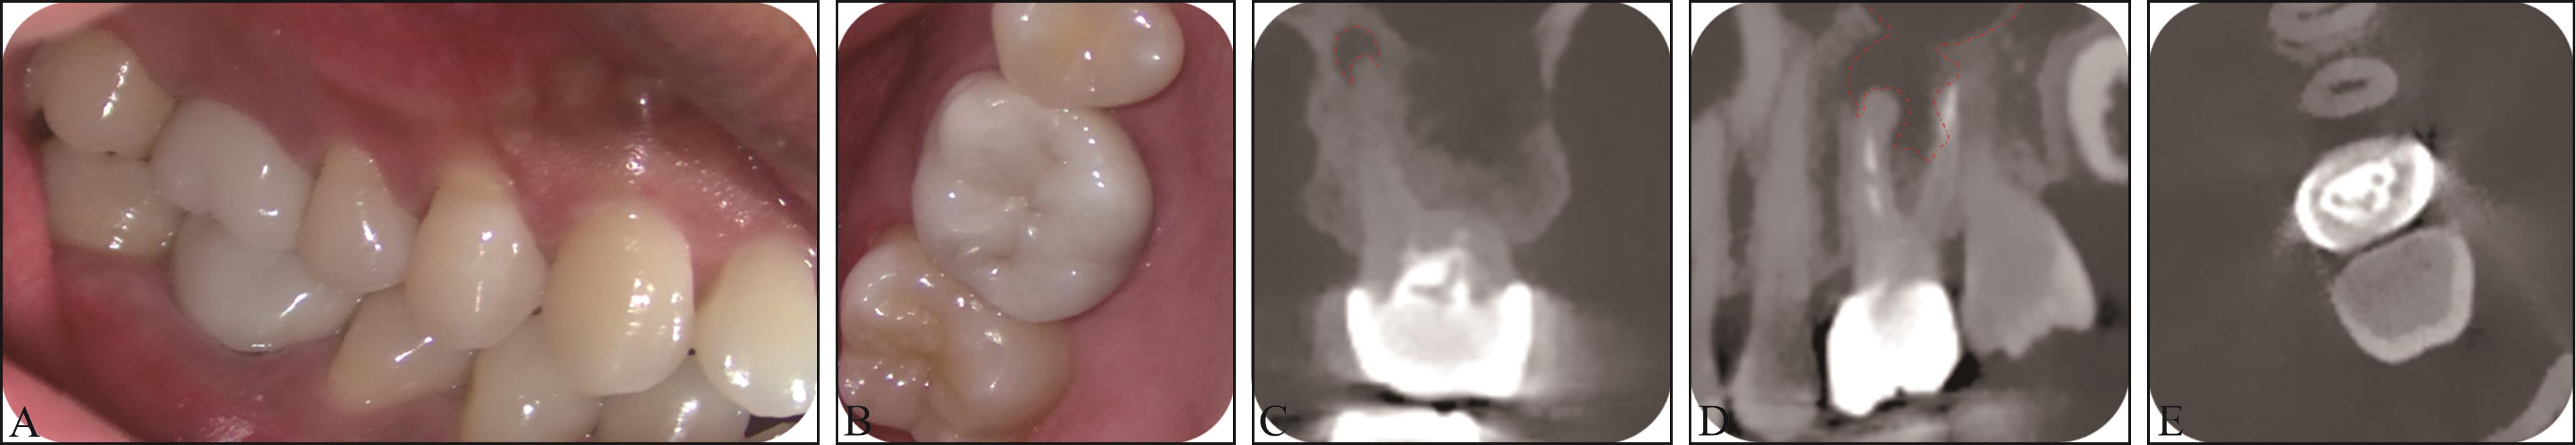

Riad Deglow E, Lazo Torres NZ, Gutiérrez Muñoz D, et al. Influence of Static navigation technique on the accuracy of autotransplanted teeth in surgically created sockets[J]. J Clin Med, 2022, 11(4): 1012.

|